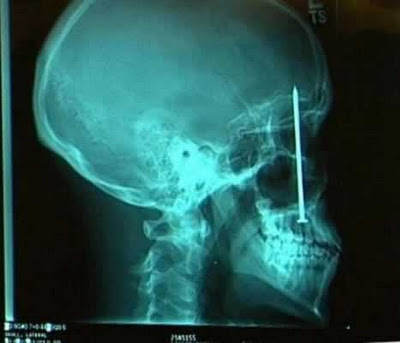

A dentist found the source of the toothache Patrick Lawler was complaining about on the roof of his mouth: a four-inch (10-centimeter) nail the construction worker had unknowingly embedded in his skull six days earlier.